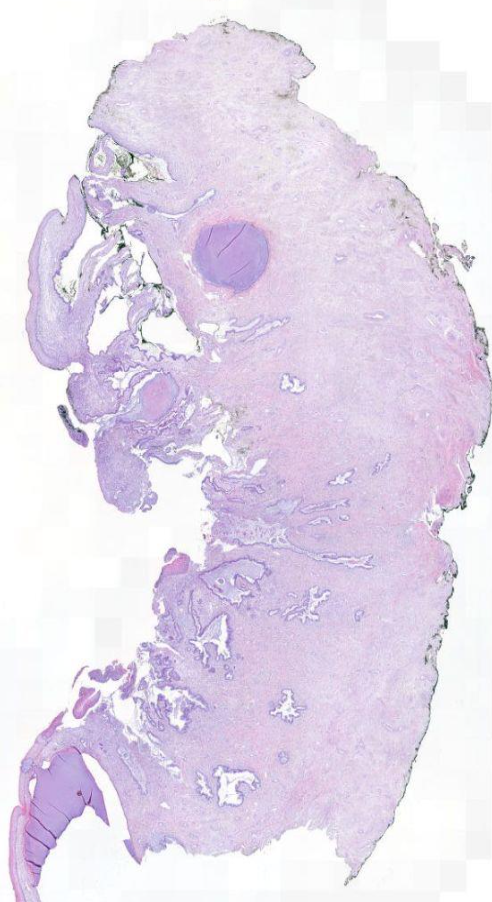

Diagnose?

Duktales Carcinoma in situ